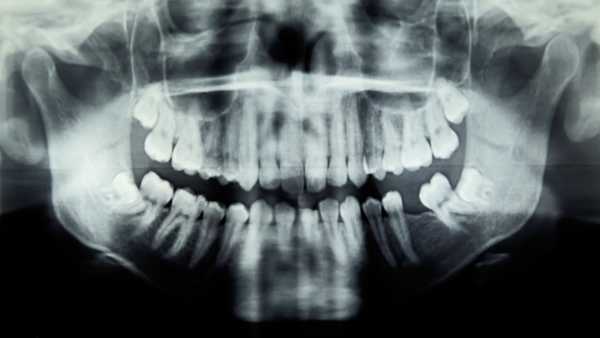

Проблеми з зубами у дівчинки спричинили небезпечну для життя інфекцію ока